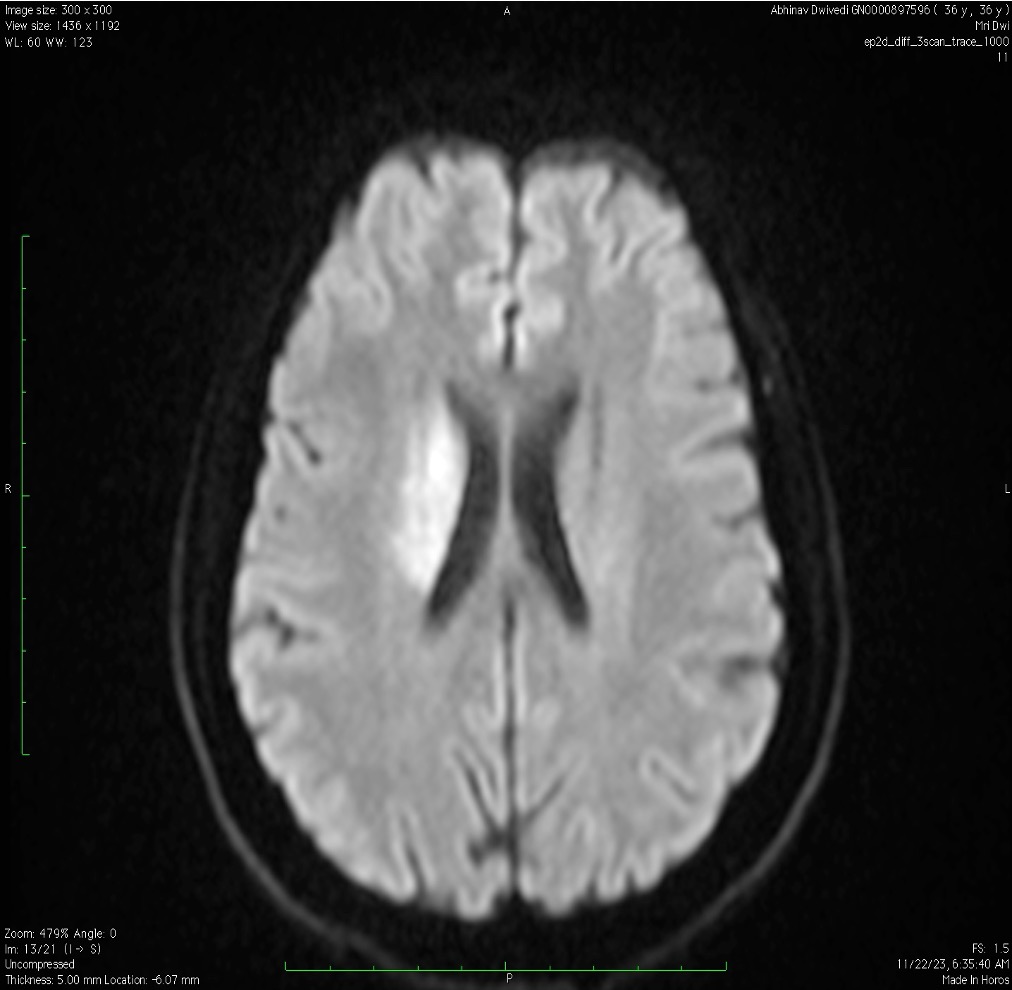

MRI Brain (DWI/ADC sequences):

Diffusion-weighted imaging — which highlights areas of fresh brain injury with high sensitivity — confirmed an acute infarct in the right Globus Pallidus and right Putamen (a region in the deep part of the brain called the basal ganglia, responsible for movement coordination and motor control).